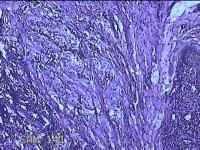

右侧手掌肉芽组织

性别

女

年龄

48岁

临床诊断

手掌开放性损伤

一般病史

右侧手掌肉芽组织增生

标本名称

大体所见

灰白暗红色带皮肤样组织1.3x0.8x0.3cm一块,切面灰白粉红色,质软。

图2